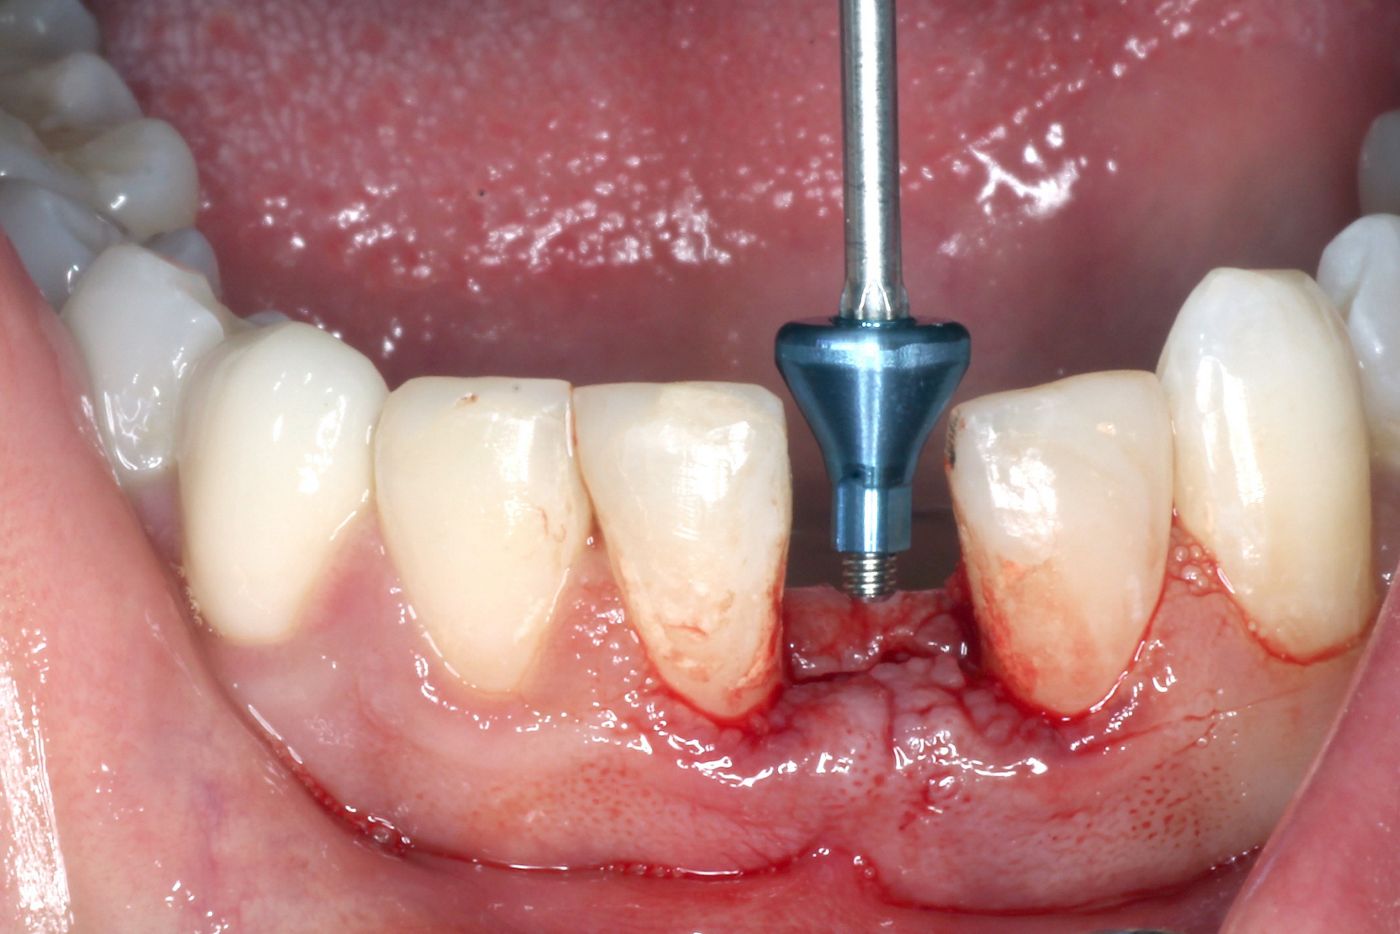

After the administration of local anesthetics, a small midcrestal incision – without releasing incisions – was made. The osteotomy was prepared using the new 1.6mm needle drill and finished using the 2.2mm pilot drill (Figs. 5,6). Since the bone was soft, no profile drill or tap was employed. The osteotomy was created within the bony envelope, and the future implant site was surrounded by native bone, although a slight buccal contour change was discernible (Fig. 7). A Straumann® BLT SC 2.9mm/12mm SLActive® implant was selected and inserted in the correct buccal orientation (Figs. 8-10). Although the implant was surrounded by bone, due to the contour dip it was decided to augment the buccal contour (Fig. 11). In view of the shape of the lower incisors and the limited space, a special asymmetrical two-piece healing abutment was designed by the manufacturer and placed accordingly (Figs. 12,13). After abutment insertion the buccal contour was augmented using a slowly resorbing DBBM-graft (Fig. 14). Two single interrupted sutures (polypropylene 6-0) were used to close the surgical site. Directly after surgery a periapical radiograph was obtained to verify the implant position (Fig. 15).